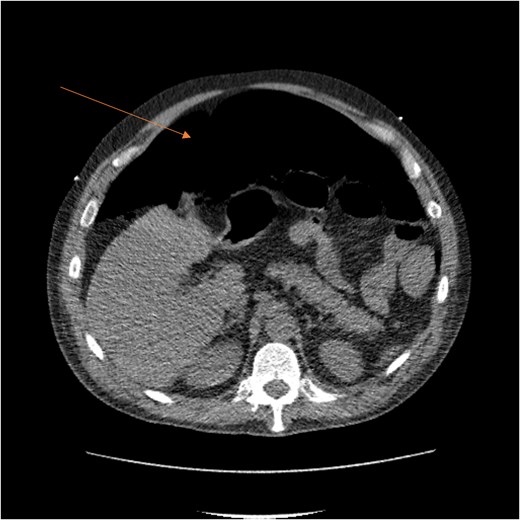

By hospital day 6, the patient’s condition improved. He was weaned from mechanical ventilation, his renal function improved (creatinine declined to 0.7 mg/dl), and hemoglobin stabilized at 8.4 gm/dl. The patient was clinically stable, and on hospital day 8, he was set up for discharge to a rehabilitation institution. However, on this day, he developed generalized abdominal pain associated with tachycardia, pulse = 118, and leukocytosis (white blood cells = 14.8 × 109/l). Physical exam revealed a distended abdomen with diffuse tenderness and sluggish intestinal sounds. A CT scan showed a large volume of pneumoperitoneum, minimal free fluid, and mildly dilated small bowel loops, consistent with a hollow viscus perforation with no identifiable source of perforation (Fig. 5) and a compression of rectosigmoid region against sacral promontory by the enlarged hematoma (Fig. 6). The right colon was decompressed compared with the prior study, and the RSH size remained unchanged, but there was progression of VTE burden. Prior to the acute deterioration, the patient had intermittently reported mild abdominal discomfort, which was initially attributed to the known RSH. There were no clinical signs suggestive of bowel obstruction, such as vomiting or significant abdominal distension. While the patient noted some degree of constipation, he reported that this was consistent with his baseline bowel habits and did not raise concern for new pathology.

CT scan demonstrating compression of large bowel (arrows) by the enlarged hematoma.